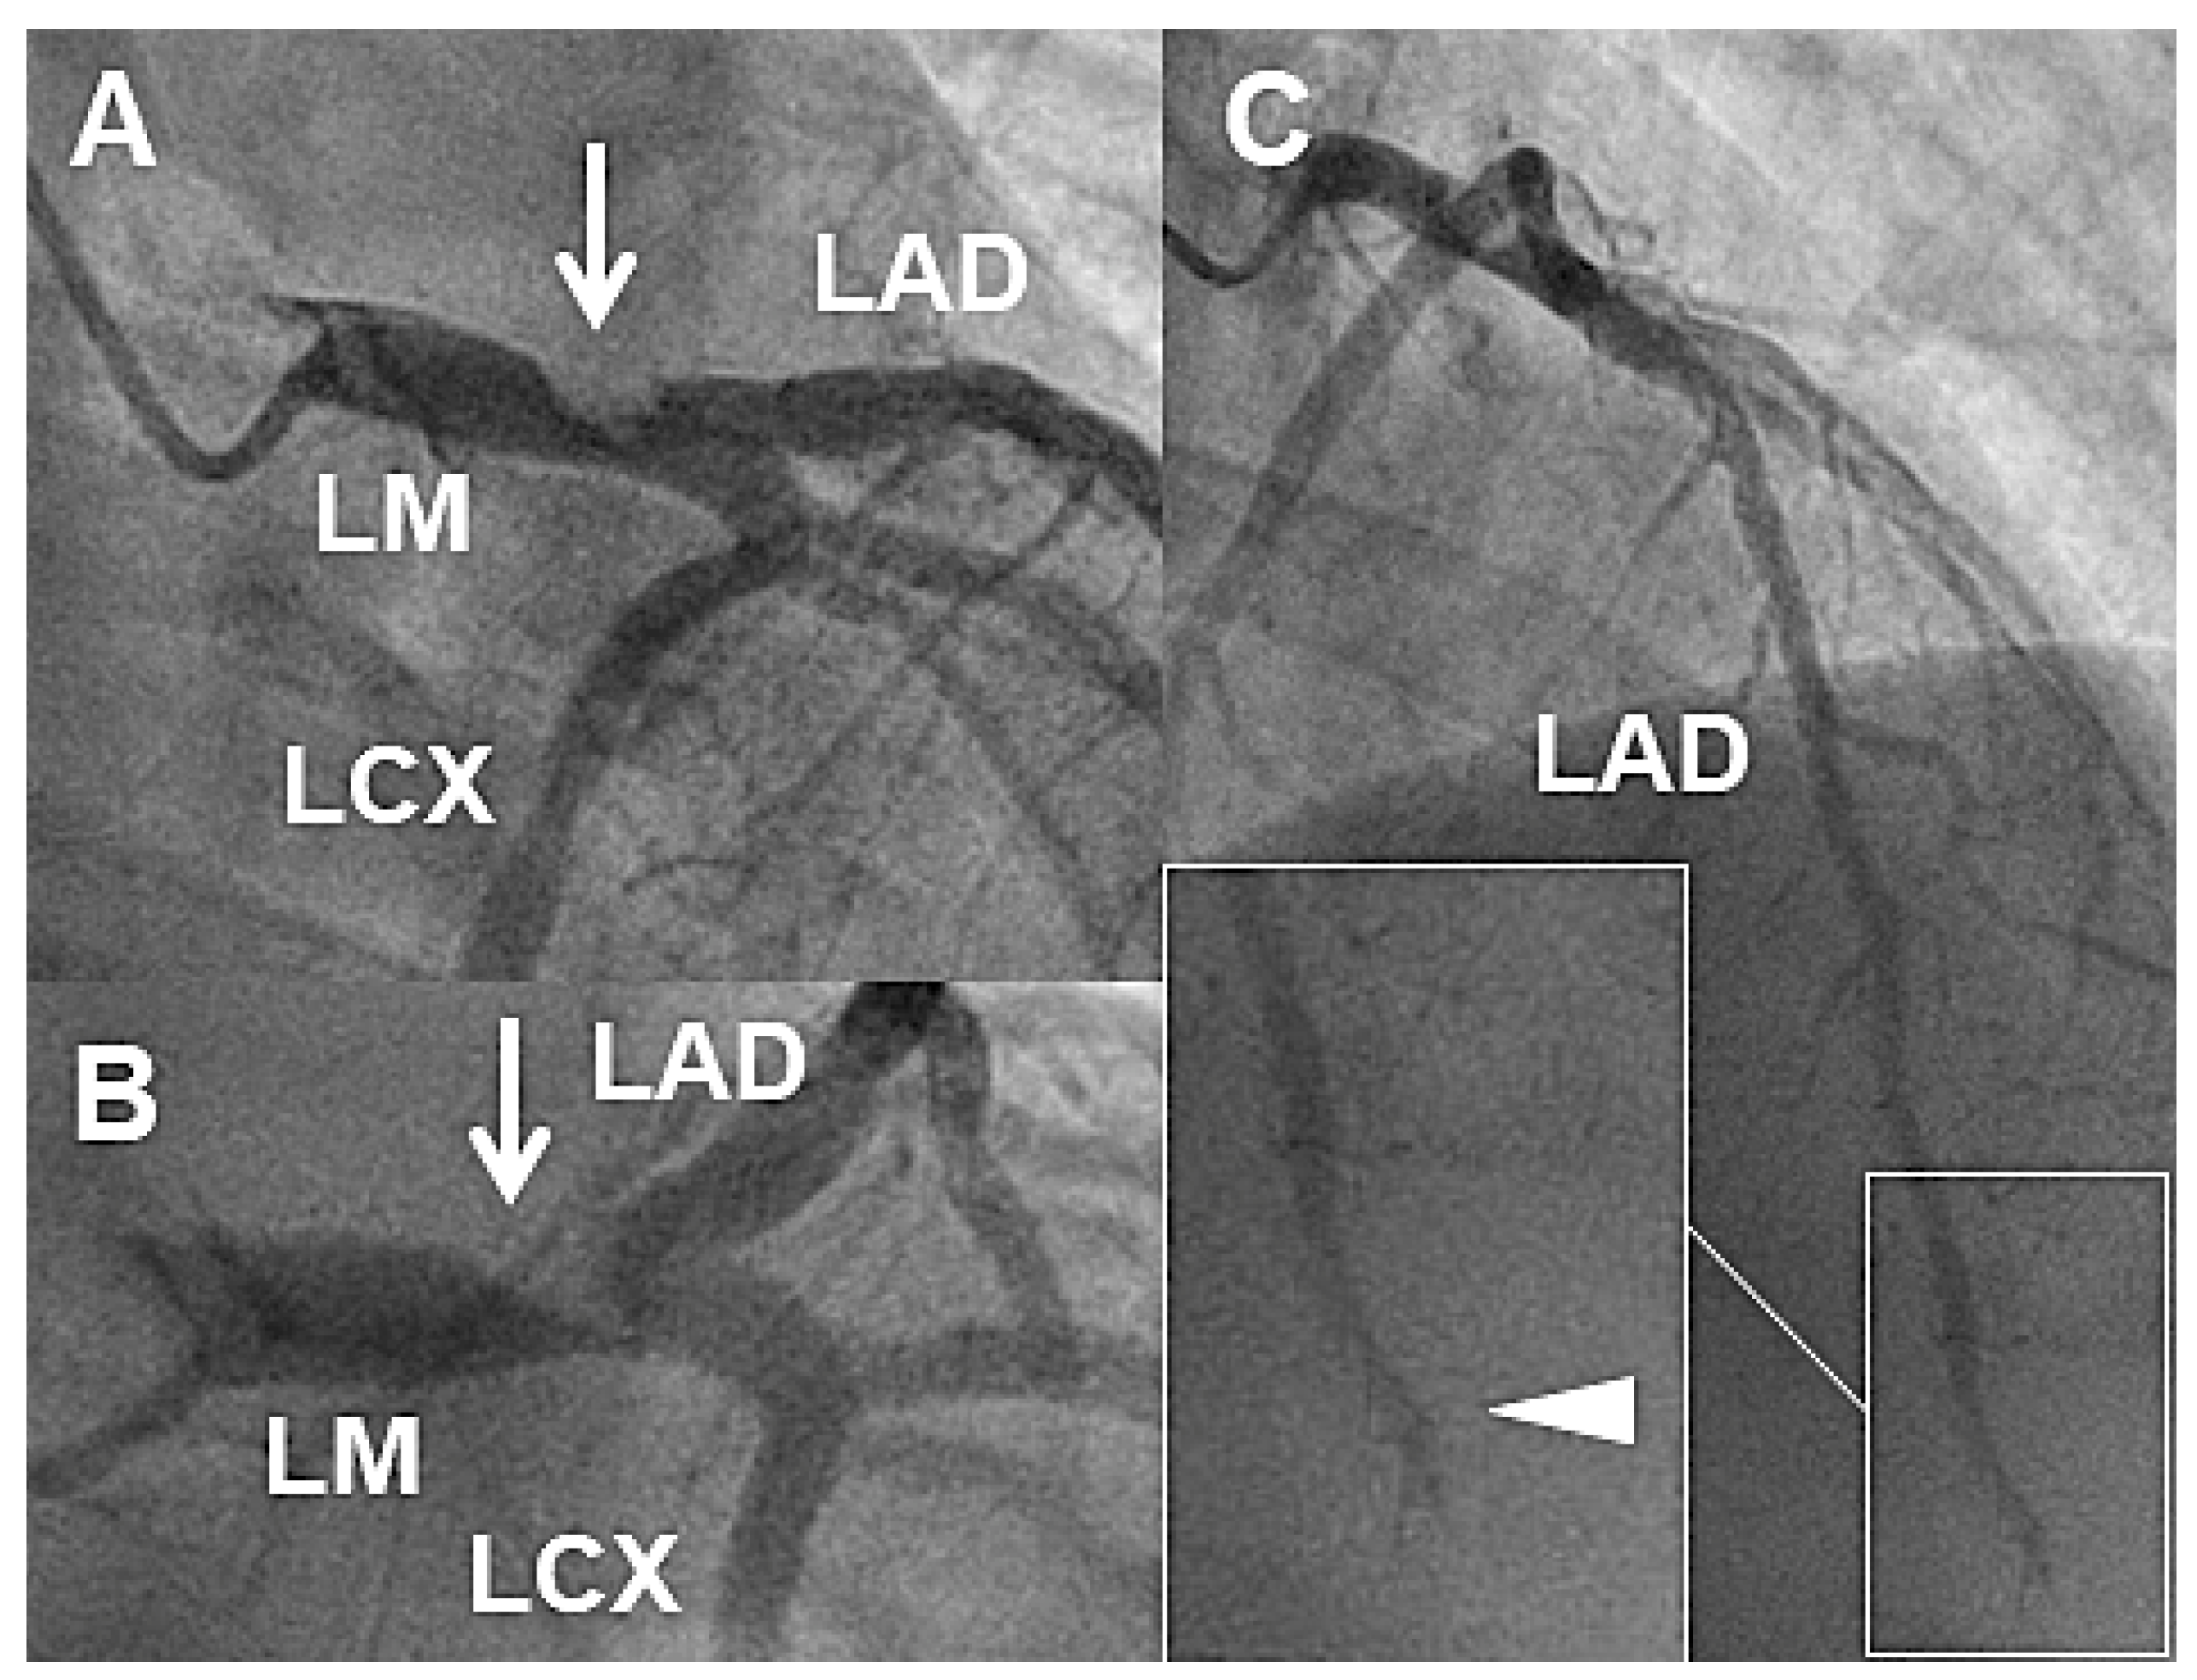

Case 1